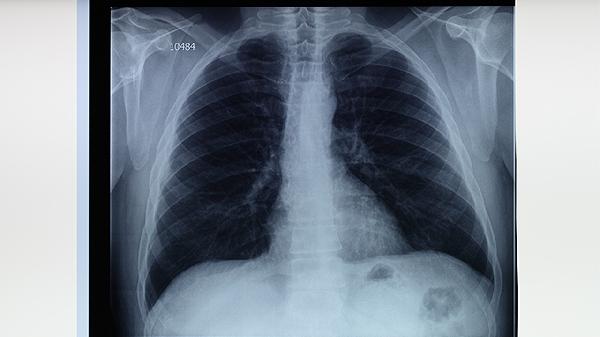

肺結(jié)核的癥狀特征主要有咳嗽、咳痰、咯血、胸痛、發(fā)熱等。肺結(jié)核是由結(jié)核分枝桿菌感染引起的慢性傳染病,主要通過呼吸道傳播,患者需及時就醫(yī)治療。

肺結(jié)核患者早期常出現(xiàn)持續(xù)性干咳,隨著病情進展可能轉(zhuǎn)為咳痰??人酝ǔ3掷m(xù)兩周以上,夜間或晨起時加重??人钥赡芘c結(jié)核分枝桿菌刺激支氣管黏膜有關(guān),痰液可能帶有血絲?;颊呖勺襻t(yī)囑使用異煙肼片、利福平膠囊、吡嗪酰胺片等抗結(jié)核藥物進行治療。

肺結(jié)核患者咳出的痰液多為白色黏液痰,病情嚴重時可呈黃綠色膿性痰。痰中可能帶有血絲或血塊,部分患者可能出現(xiàn)大量咯血。咳痰癥狀通常伴隨咳嗽出現(xiàn),痰液檢查可發(fā)現(xiàn)結(jié)核分枝桿菌。患者需注意保持呼吸道通暢,避免痰液堵塞氣道。

肺結(jié)核患者可能出現(xiàn)痰中帶血或大量咯血,這是由于結(jié)核病灶侵蝕肺部血管所致。咯血量可從少量血絲到大量鮮血不等,嚴重時可危及生命。患者出現(xiàn)咯血時應立即就醫(yī),醫(yī)生可能會建議使用止血藥物如氨甲環(huán)酸注射液,同時繼續(xù)抗結(jié)核治療。

肺結(jié)核患者常感到胸部隱痛或刺痛,疼痛多位于病變部位。胸痛可能與胸膜受累或肺部炎癥刺激有關(guān),深呼吸或咳嗽時疼痛可能加重。部分患者可能出現(xiàn)胸腔積液,導致呼吸困難。醫(yī)生可能會建議使用對乙酰氨基酚片緩解疼痛,同時進行抗結(jié)核治療。

肺結(jié)核患者通常出現(xiàn)午后低熱,體溫多在37.5-38.5攝氏度之間。發(fā)熱可能伴有盜汗、乏力等癥狀,夜間出汗后體溫可自行下降。發(fā)熱是機體對結(jié)核分枝桿菌感染的免疫反應,隨著抗結(jié)核治療的有效進行,發(fā)熱癥狀會逐漸緩解。